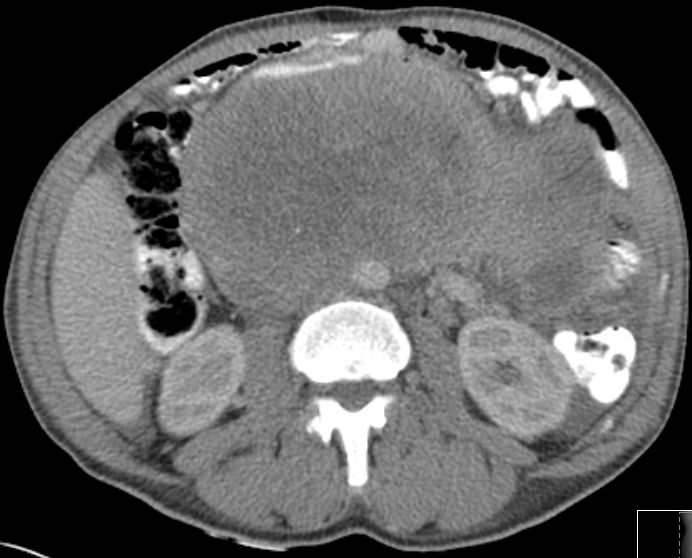

| retroperitoneal | 43-jähriger Mann mit großer Raumforderung im Abdomen.

Undifferenziertes Weichteilsarkom.![]() |